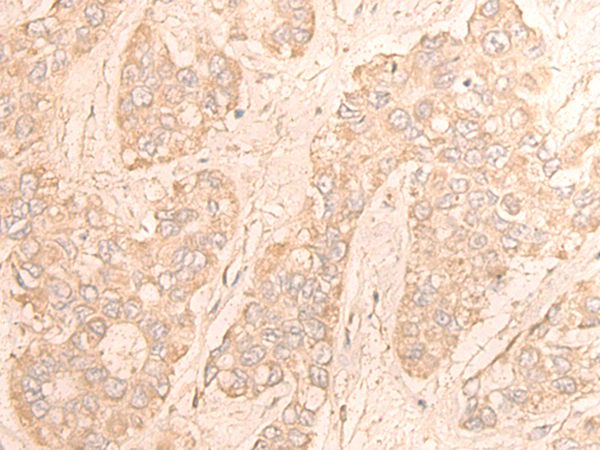

分类: 科研抗体货号: P43586别名: GPCR; PGR7; GALR4; GALRL; GPCR-2037应用: IHC反应种属: Human